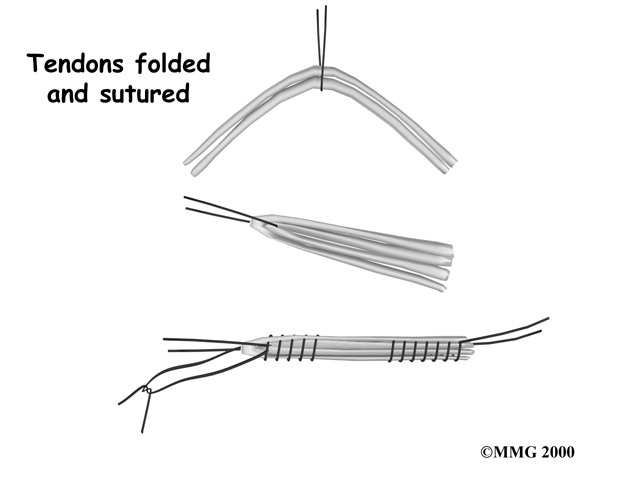

Hamstring Tendon Graft

Surgeons also commonly use a hamstring graft to reconstruct a torn ACL. This graft is taken from one of the hamstring tendons that attaches to the tibia just below the knee joint. The hamstring muscles run down the back of the thigh. Their tendons cross the knee joint and connect on each side of the tibia. The graft used in ACL reconstruction is taken from the hamstring tendon, called the semitendinosus. This tendon runs along the inside part of the thigh and knee. Surgeons also commonly include as part of the hamstring graft a tendon just next to the semitendinousus, called the gracilis.

Hamstring Graft

When arranged into three or four strips, the hamstring graft has nearly the same strength as a patellar tendon graft.